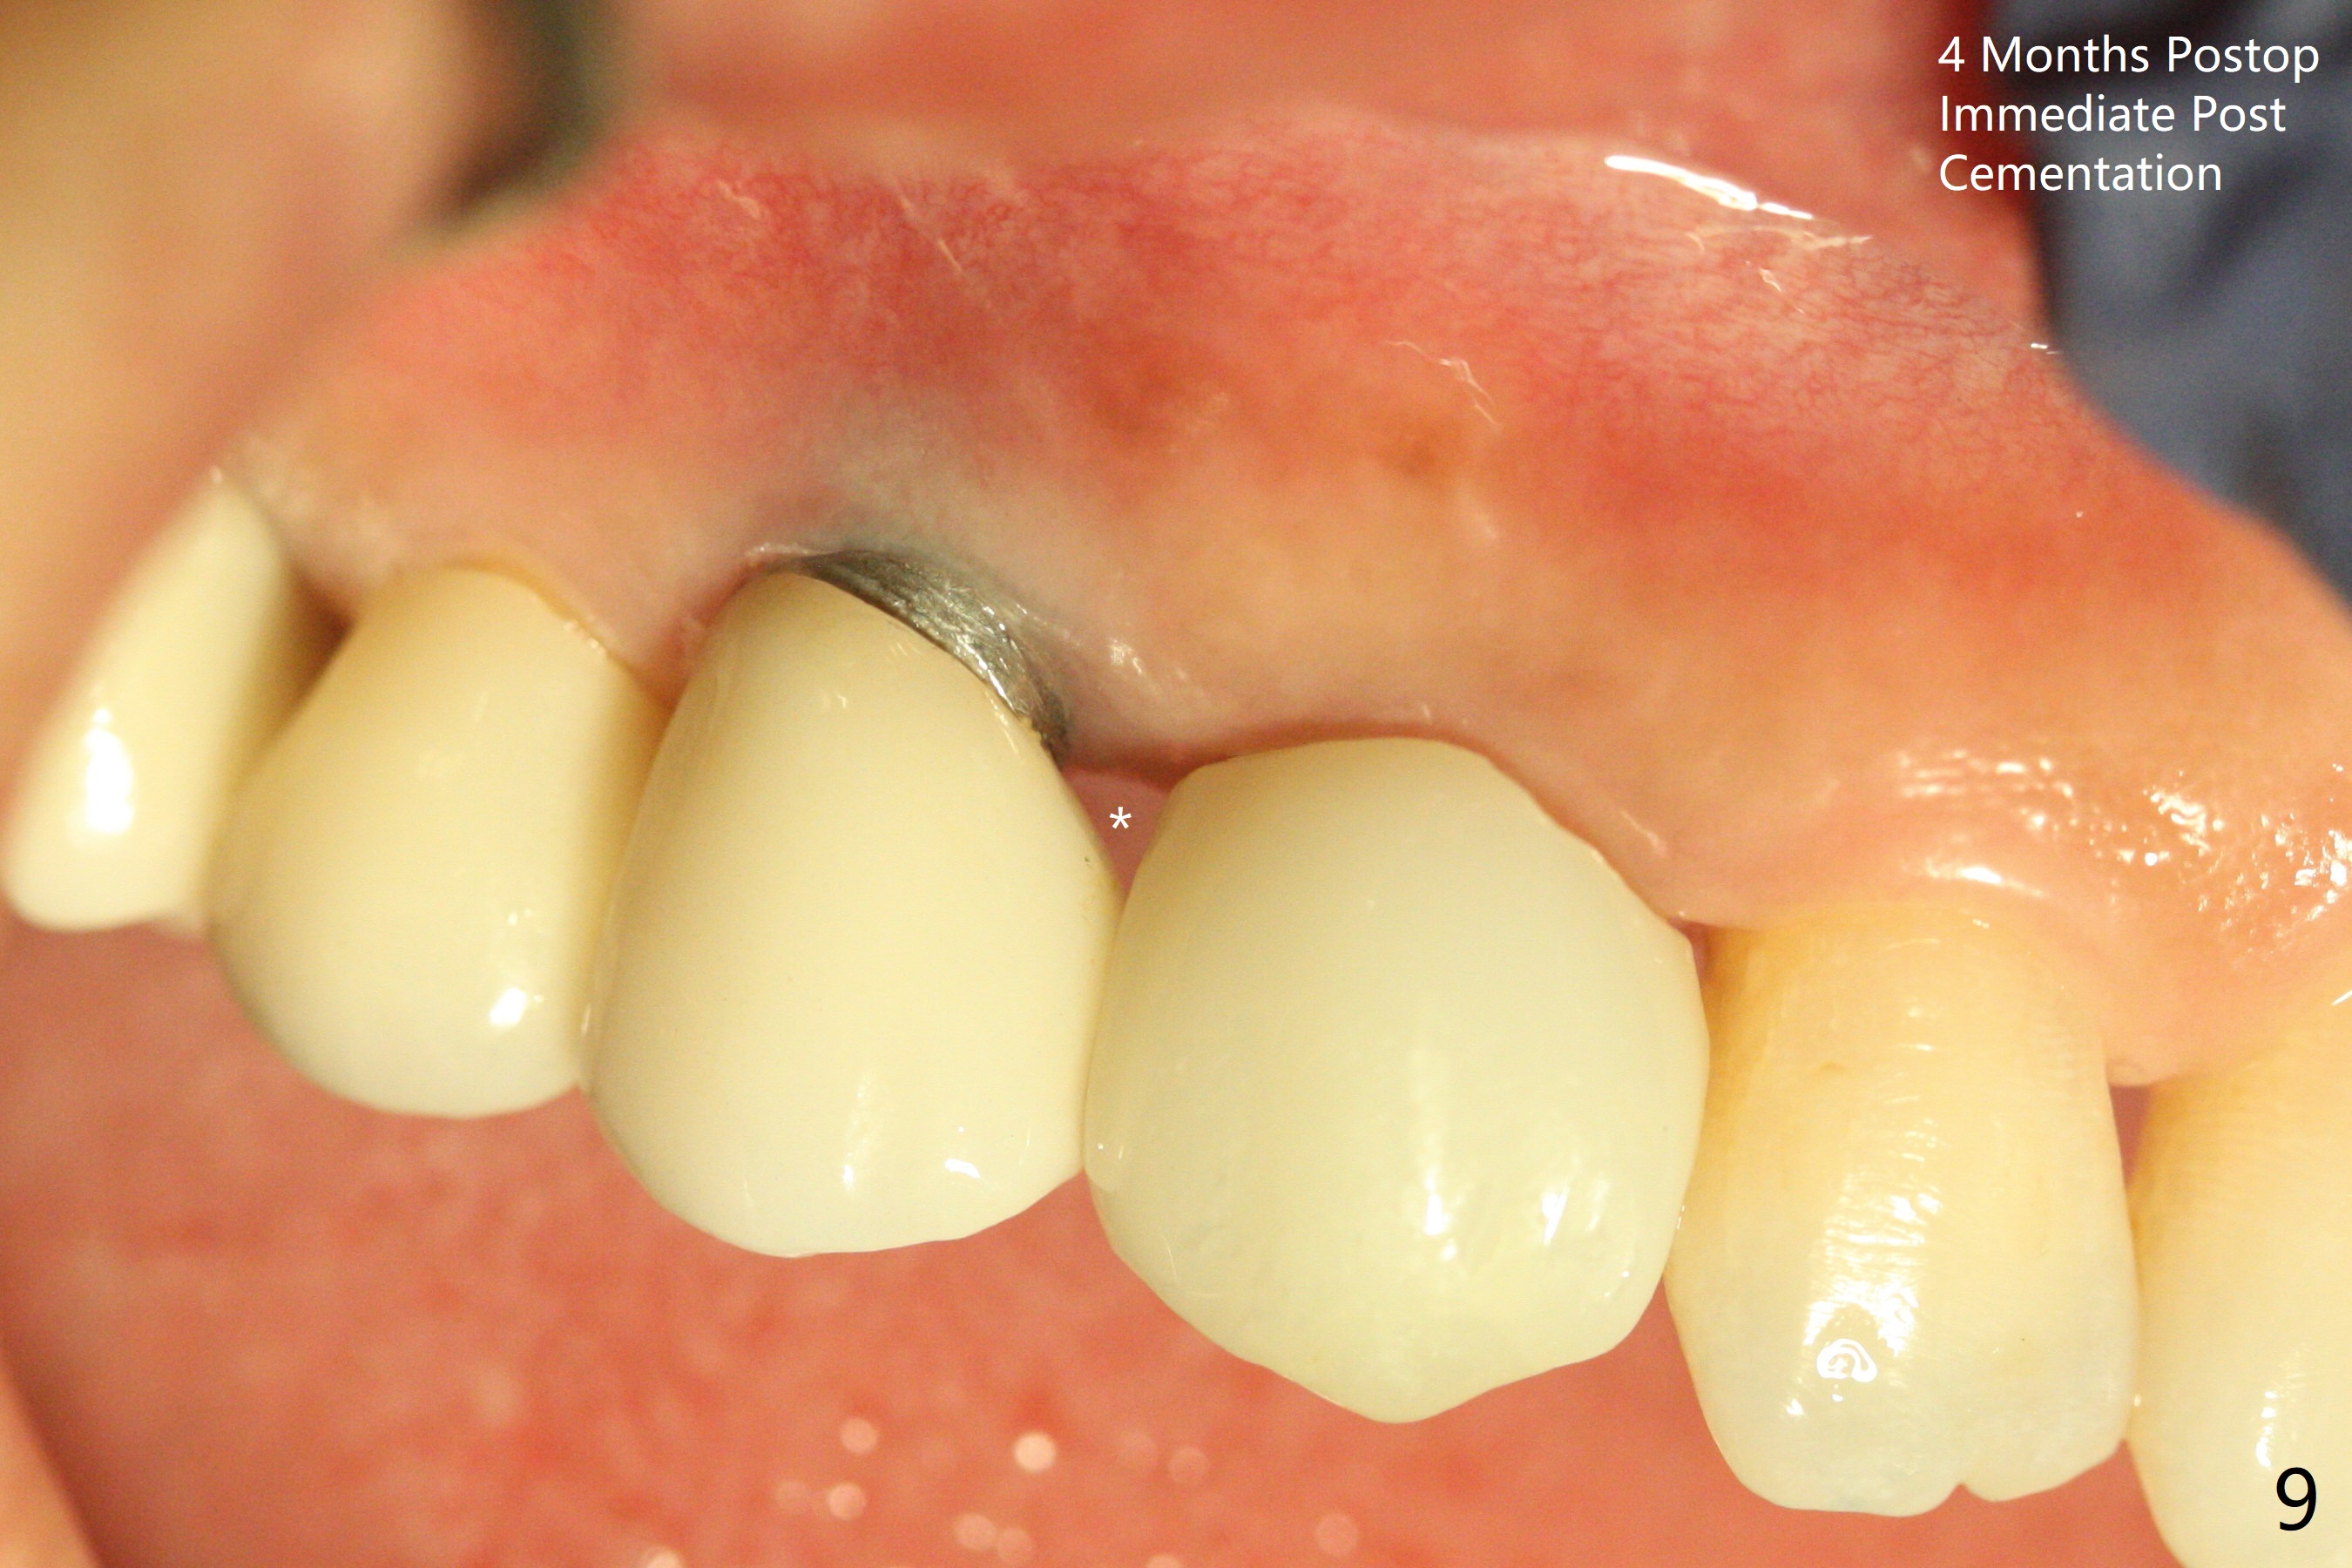

When the recemented crown at #6 is removed, the post is found to have been fractured. When the tooth is extracted, the socket walls are found intact. After moving the initial osteotomy (Fig.1) mesial, a 3.8x13 mm implant is placed (Fig.2). Clinically it appears supracrestal lingually. So the implant is placed deeper, but a cemented abutment is incompletely seated (Fig.3 <). When a longer abutment is used (easy grasping), it is seated completely (Fig.4). Then sticky bone is packed (Fig.5 *). When an immediate provisional is fabricated and seated, PRF membranes are inserted into the remaining gap between the gingiva and the provisional. Free hand surgery takes time and more intraop X-ray. It is inconvenient with nervous patients. The socket heals 2 weeks postop (Fig.6). The provisional will be next relined and reseated. It is difficult to insert gingival retraction cord 3.5 months postop because of the deep mesial margin. When an abutment with longer cuff is placed, the packing is easier (no biologic width violation, Fig.7 (^: resorbed mesial crest), as compared to Fig.5). When the crown is cemented (un-esthetic due to failure of use of temporary abutment), the metal shows at #5 with gingival recession because of buccal placement (Fig.8-10). Bone resorption is severe between #5 and 6 (Fig.7), as related to large gingival embrasure (Fig.9 *). When #5 crow is redone, move the gingival margin apical and fabricate provisional.